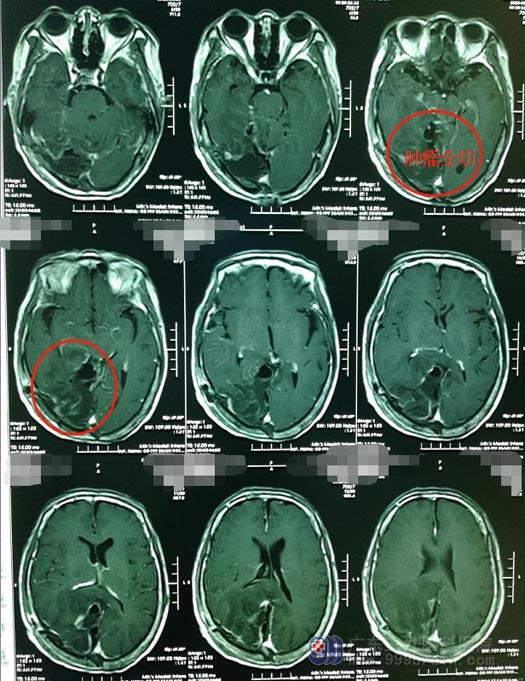

▲术后MRI

术后,梁奶奶很快就麻醉清醒,手脚运动灵活,目前在稳步恢复中。奶奶对自己可爱地竖起大拇指:我就是不认命。